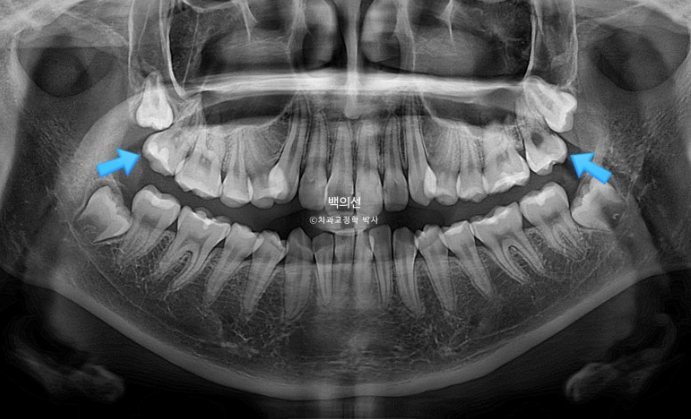

23.05

송곳니 덧니가 심한편입니다.

맨 뒤 큰어금니는 뒤로 나있습니다.

파란 화살표 위 마지막 큰어금니는 매복된 사랑니에 눌려 사랑니를 발치하지 않으면 바로세우기 힘든상황입니다.

그런데 씨티를 찍어보니 매복된 사랑니가 상악동과 닿아있어 발치가 쉽지 않은 상황입니다.

무리하게 발치를 시도했다가 상악동천공 등의 부작용이 생길 수 있습니다.